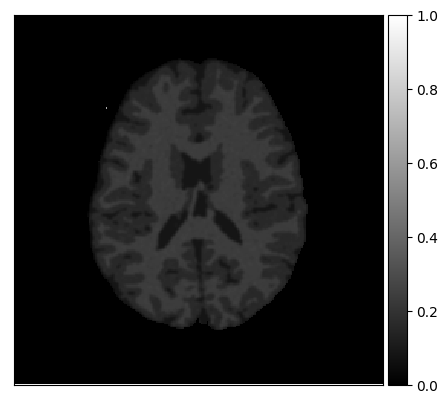

Appendix A describes the nuclear magnetic resonance (NMR) relaxation times for the tissues in the Brainweb anatomical models, for 1.5 and 3.0 Tesla field strengths. The tissues in the anatomical models are grouped into ”background” (BKG), ”cerebrospinal fluid” (CSF), ”gray matter” (GM), and ”white matter” (WM) to compose the ground truth segmentation labels for the simulated scans. The simulations result in images of 256 by 256 pixels, with a 1.0x1.0mm resolution. Figures 5(a) and 5(b) show examples of the Brainweb1.5T and Brainweb3.0T scan of the same subject. For all scans, we used a brain mask to strip the skull.

In order to test the proposed method on real data, we use the publicly available training data (5 subjects) from the MRBrainS challenge444http://mrbrains13.isi.uu.nl/Figure. The acquisition parameters used for simulating the Brainweb3.0T are based on the MRBrainS acquisition protocol (3.0T scanner, gradient-echo, B0 = 3.0T, = flip angle, TE = 4.5ms, and TR = 7.9ms). Figure 5(c) shows an example of an MRBrainS scan. Again, a brain mask is used to strip the skull.

Figure 7 (left) shows the proxy -distance between the source and target samples for all three experiments. The proxy -distance for experiments 2.1 and 2.2 shows that in the original representation (raw; red line), the source and target distributions lie far apart (proxy -distance approaches ). This illustrates the difference in acquisition protocol (1.5T versus 3.0T). After applying mrai-net (rep; blue line) the proxy -distance drops drastically (approaches ) showing that the network managed to learn an MR-acquisition invariant representation. Adding more target training samples improves the invariance up to about 100 samples, but the proxy -distance is already quite low after only using 1 target sample per tissue type for training. In experiment 2.3 the proxy -distance before applying mrai-net (raw) is already much lower than in the previous two experiments (around ), this illustrates that the acquisition protocols are more similar to begin with (both 3.0T). The main difference between the distributions presumably results from simulated versus real data, since not all factors of acquisition variation are included in the simulations, most notably partial volume (0.96x0.96x3mm voxels in MRBrainS versus no partial volume in Brainweb). However, after applying mrai-net the proxy -distance is reduced further (approaches ), again showing that mrai-net is able to learn an MR-acquisition invariant representation (rep) on this data, even for simulated and real data. Note that the MRBrainS data adds other modes of variation in terms of pathology and age in comparison to the Brainweb healthy adults, which could influence the tissue classification performance.

Figure 7 (right) shows the tissue classification error for all three experiments. If the proxy -distance between the source and target distribution is high (experiment 2.1 and 2.2), and when using only one target sample per tissue, the source classifier that uses both the source data and target data for training shows worse performance than the one that uses only the target data (target); an error of 0.667 versus 0.591, respectively. Even when adding more target samples for training, the results show that it is more beneficial to train a supervised classifier on the target data alone, instead of on both the source and target data; using 10 target samples for training, source achieves an error of 0.662 versus an error of 0.403 for target. The source classifier is focused on its source samples, which in this case are not informative of the target data. Given enough target samples, however, source starts to shift focus towards its target data and starts to match the performance of target: for 100 target samples, errors of 0.213 versus 0.205 respectively. If the proxy -distance between the source and target distributions is low (distributions are more similar; experiment 2.3), using the source data for training is beneficial; for 1 target sample per tissue source achieves an error of 0.435 and target an error of 0.596. In this case, the source samples are more representative of the target data and are aiding the classifier. In general, the mrai-net classifier outperforms both the source and target classifiers: an error of 0.269 for 1 sample, 0.175 for 10 samples and 0.111 for 100 samples. mrai-net’s representation ensures that the source and target samples are more similar and that the source samples can be effectively used for training.